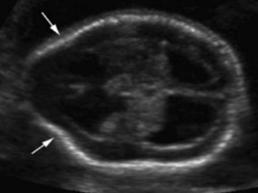

Certeza: La ecografía transvaginal es la prueba confirmatoria de embarazo. A las 4.5 semanas, se observa saco gestacional; a las 5 semanas, se encuentra embrión, y a las 6 semanas es posible auscultar los latidos cardiacos fetales con el doppler . También se considera la percepción de movimientos fetales por parte del médico.

Figura 11. Ecografía de I trimestre Examen de certeza para confirmar un embarazo eutópico y viable

En la del I trimestre (10-14 semanas), se confirman la gestación, la edad gestacional de forma más precisa midiendo la longitud craneocaudal (LCC)

(ENAM EXTRA 2021), y la vitalidad del embrión (actividad cardiaca) (ENAM EXTRA 2020)

Es considerada la ecografía más importante por 3 propósitos:

Evaluación de riesgo genético (riesgo de cromosomopatías o aneuploidías)

Evaluación morfológica (exclusión de malformaciones visibles en el 1er trimestre)

Evaluación de riesgo de preeclampsia y RCIU.